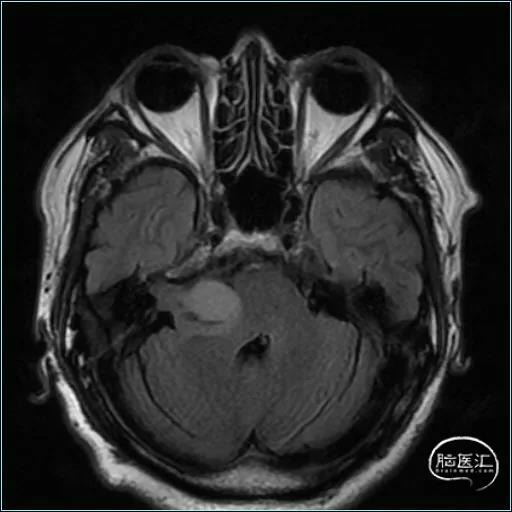

术前影像资料

五年前因听力下降,核磁共振检查发现听神经瘤

最大径约3.0cm,行右侧听神经瘤切除术

现患者出现右边脸部麻木6个月,复查磁共振提示肿瘤复发

最大径约3.9cm